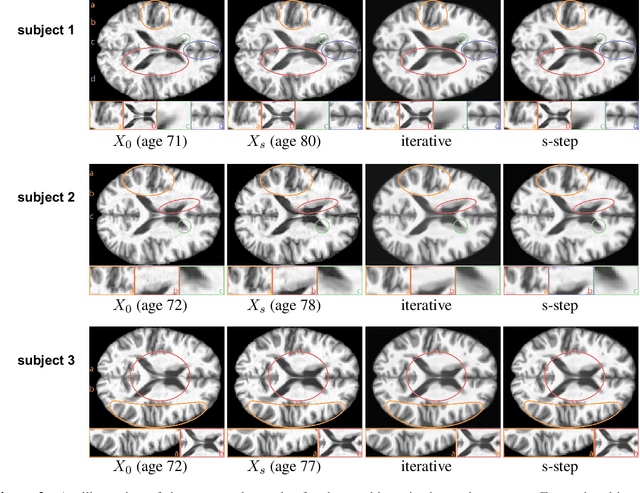

Abstract:This paper focuses on the analysis of sequential image data, particularly brain imaging data such as MRI, fMRI, CT, with the motivation of understanding the brain aging process and neurodegenerative diseases. To achieve this goal, we investigate image generation in a time series context. Specifically, we formulate a min-max problem derived from the $f$-divergence between neighboring pairs to learn a time series generator in a nonparametric manner. The generator enables us to generate future images by transforming prior lag-k observations and a random vector from a reference distribution. With a deep neural network learned generator, we prove that the joint distribution of the generated sequence converges to the latent truth under a Markov and a conditional invariance condition. Furthermore, we extend our generation mechanism to a panel data scenario to accommodate multiple samples. The effectiveness of our mechanism is evaluated by generating real brain MRI sequences from the Alzheimer's Disease Neuroimaging Initiative. These generated image sequences can be used as data augmentation to enhance the performance of further downstream tasks, such as Alzheimer's disease detection.